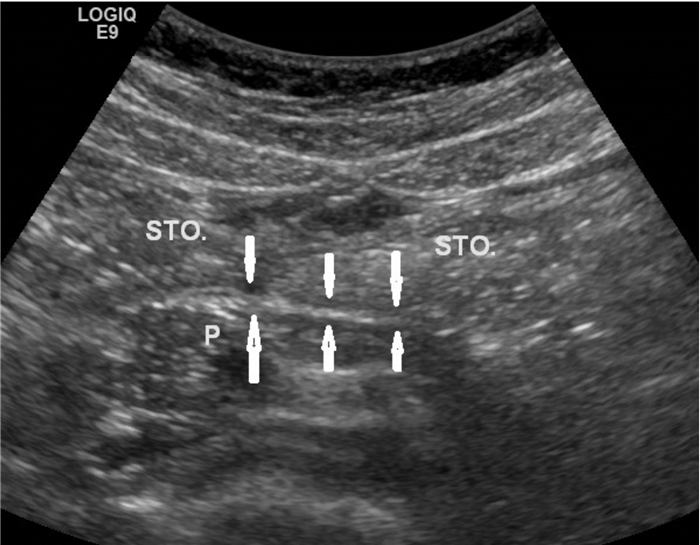

1.4 小网膜囊增厚超声判断标准:正常情况下,小网膜囊超声不显示(图 1),以胰胃间距增加作为小网膜囊增厚的判断标准。

| 上排箭头:胃后壁,其浆膜面构成网膜囊前壁;下排箭头:胰腺前缘,构成网膜囊后壁;STO:胃;P:胰腺 图 1 正常情况小网膜囊超声图示 |